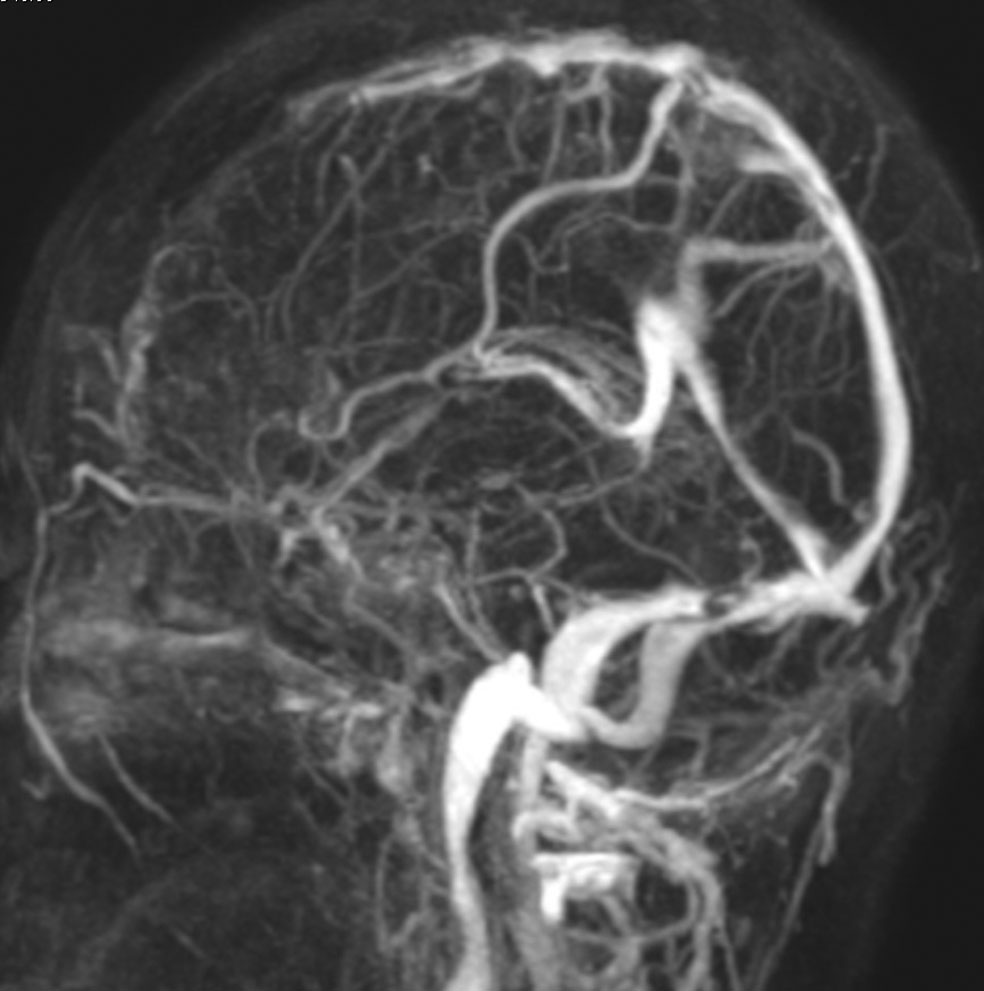

片側髄膜腫症 unilateral meningiomatosis

50歳ころから15年間に3回の開頭手術を受けている患者さんです。parasagittal, falx, convexityなど6個の髄膜腫がすでに摘出されています。左側だけ,テント上だけに髄膜腫が20個くらい多発していました。これらはグレード1で,anaplastic meningiomaの転移ではありません。

やがて蝶形骨縁の髄膜腫の増大速度が早まりatypical meningiomaとなりました。MIB-1 index が10%の高値でした。病理学的にも,psamomatous meningiomaなど様々な種類の髄膜腫が多発しています。

初発時から多発性髄膜腫であり,最初の手術で左側テント上の硬膜を広範囲に摘出しておくべきでした。このような病態は若年者でもみられることがあり,胎生期の硬膜の原基になる細胞にmutationが生じたとしか考えづらいものです。